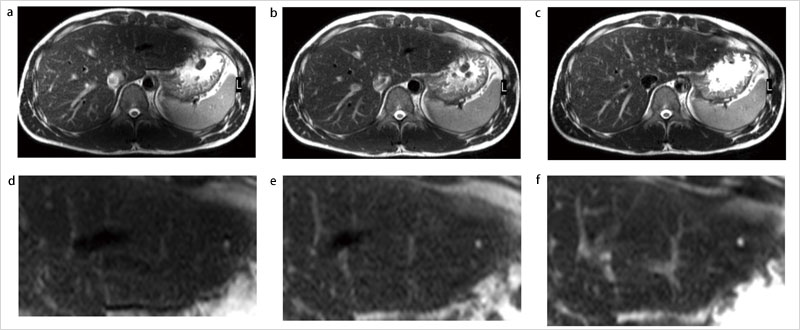

図5に,3.0Tで得られた腹部画像を示す。図5 aでは,信号強度が極端に低下している領域が認められている。これが,3.0Tで問題となるRFパルスの不均一に伴う信号低下である。図5 bは,プリスキャンによって局所的なRFパルスの不均一領域を推測し,その領域の信号強度を補正するアルゴリズム(Body Tuned CLEAR:BTC)を用いて再構成を行った画像である。BTCを用いることで,図5 aに比べて信号の不均一が改善している。それに対して,図5 cはMultiTransmitを用いて得られた画像である。BTCを用いなくても,照射RFパルスをより均一にすることで,信号の顕著な低下を防いでいる。図5 d〜fは,図5 aで認められる信号低下領域を中心に,図5 a〜cそれぞれを拡大した画像である。図5 b図5 cでは,どちらも信号の均一性は高まっているが,拡大図である図5 e図5 fを比較すると,図5 f図5 eに比べて血液と周囲肝組織のコントラストが向上しているのがわかる。これは,RFパルスの不均一が生じている部位では,設定どおりのフリップアングルでRFパルス照射が行えていないため,図5 bで施されたような後処理で信号を均一化しても,コントラストまでは補正できないことを意味している。

MultiTrtansmitは,照射RFパルスを最適化することによってフリップアングルが設定値に近づくため,信号不均一だけでなく,コントラストの改善にもつながる,より抜本的な解決策であることが理解できる。

図5 MultiTransmitと従来送信法による画像コントラストの比較

a:従来送信法によって撮像された腹部画像。信号強度が極端に低下している領域を認める。

b:信号補正技術(Body Tuned CLEAR:BTC)を用いて再構成を行った画像。aに比べて信号の不均一が改善している。

c:MultiTransmitを用いて撮像した画像。BTCを用いなくても,信号の均一性が高まっている。

d〜f:aで認められる信号低下領域を中心に,a〜cそれぞれを拡大。血液と周囲肝臓組織のコントラストを比較すると,fが最も高いことがわかる。

(画像ご提供:東海大学病院様)